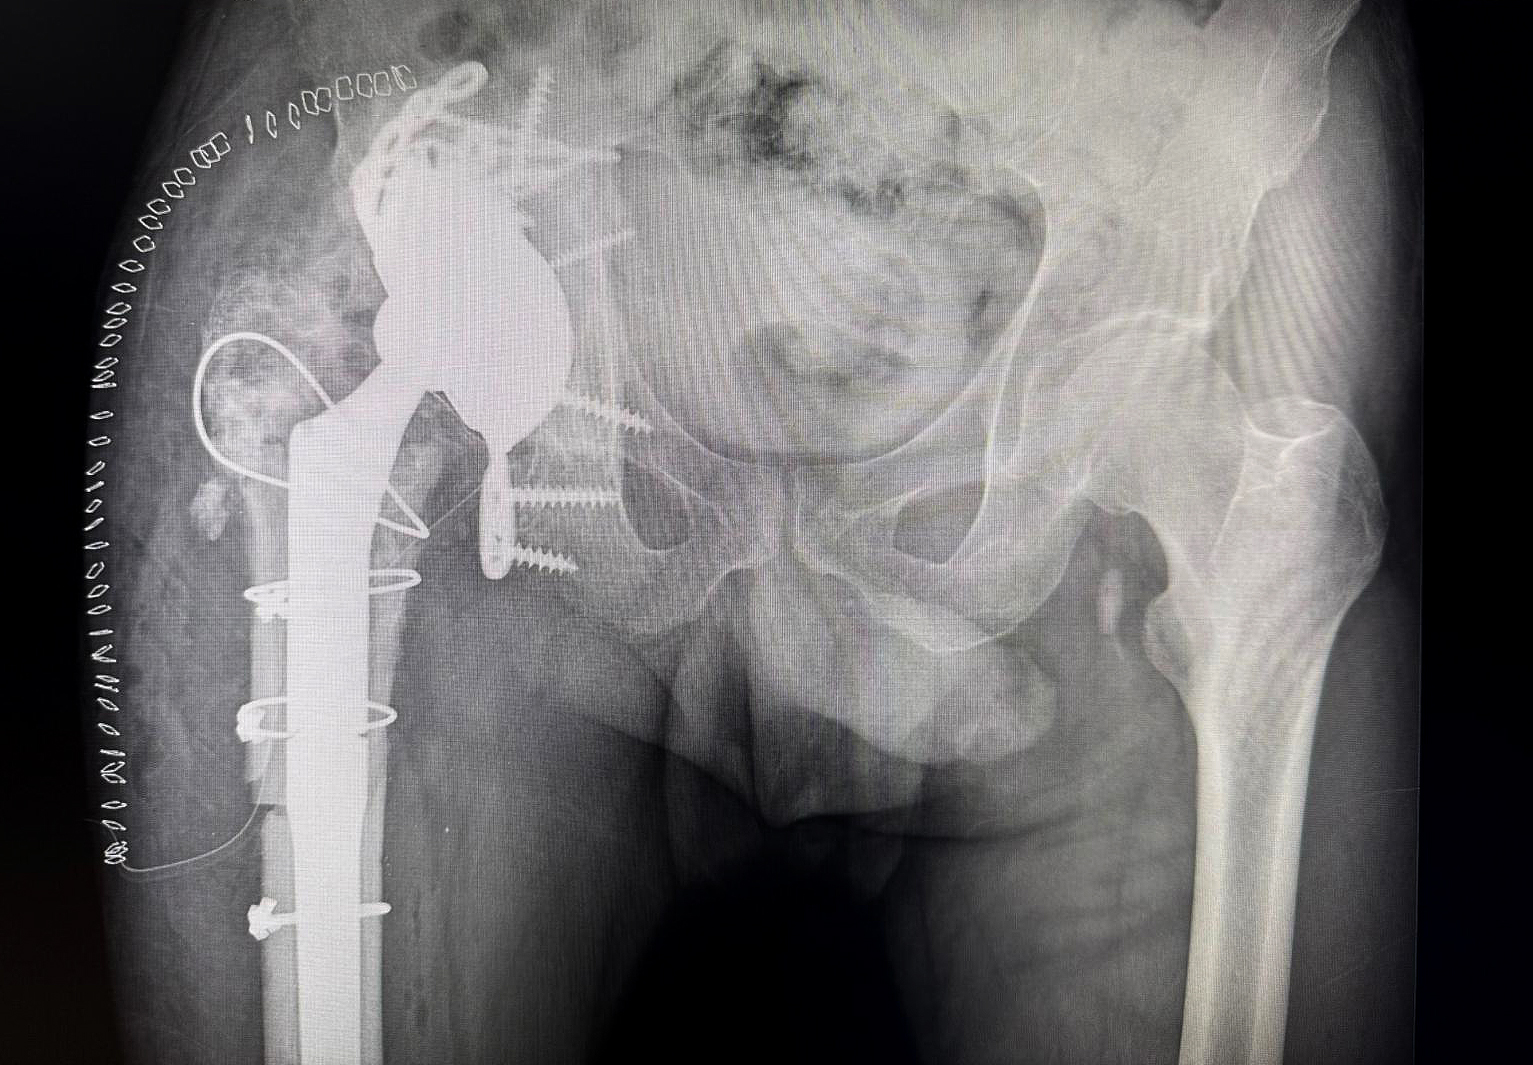

Postoperative X-ray showing integrated augment–cage construct with stable fixation, allowing early full weight-bearing.

The extreme malleable flanges allowed the cranial fixation.

Off-the-shelf MobileLink PPR using a Dual Mobility Insert, combined with a TrabecuLink Augment.

At 18 months follow-up, the patient remains asymptomatic. He ambulates without walking aids and demonstrates active hip flexion of 90 degrees. There are no clinical or laboratory signs of recurrent infection.

This case highlights the dual challenge inherent to chronic multidrug-resistant PJI in the presence of severe acetabular bone loss. Biological eradication of infection required aggressive debridement and high-dose local antibiotic delivery. Mechanical reconstruction required understanding the biomechanics of the defect rather than relying solely on classification.

The absence of the posterior wall created anteroposterior instability that could not be resolved by cranial augmentation alone. By mechanically linking a trabecular titanium augment to a PPR cage, structural logic was restored. Stability was achieved not through implant complexity but through coherent construct integration. In multiply revised hips, dual mobility articulation adds an additional layer of safety by reducing dislocation risk in compromised soft tissue environments.